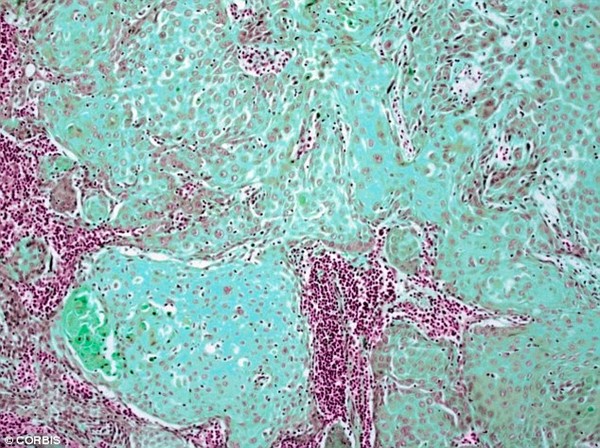

Một hợp chất trong trà xanh đă được t́m thấy và cho rằng có thể tiêu diệt tế bào ung thư miệng mà không làm ảnh hưởng đến những tế bào khỏe mạnh khác. Ảnh minh họa

EGCG có thể kích hoạt một quá tŕnh trong các ty lạp thể - các nhà máy điện của một tế bào sản xuất năng lượng - từ đó làm chết tế bào. Ảnh minh họa